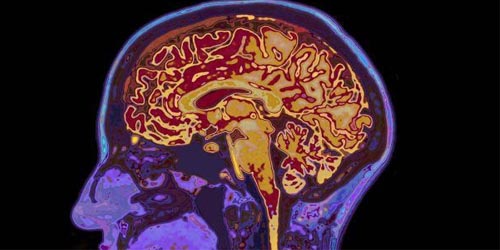

இந்த மர்ம நோயால் பாதிக்கப்படுபவர்கள் தூக்கமின்மை மற்றும் பலவீனமான நினைவக செயல்பாடுகள் மட்டுமல்லாமல், பார்வை மாயத்தோற்றங்களையும் அனுபவிப்பதாக கூறியுள்ளனர்.

இப்போதைக்கு, நோயின் தோற்றம் இன்னும் தீர்மானிக்கப்படவில்லை. இருப்பினும், செல்போன் கோபுரங்களிலிருந்து வரும் கதிர்வீச்சுதான் இந்த நோயைப் பரப்புகிறது என்று சுகாதார நிபுணர்கள் கூறி வருகின்றனர். இதுதவிர கோவிட் 19 தடுப்பூசிகள் ஒரு சாத்தியமான காரணமாக இருக்கலாம் என்றும் சிலர் கூறியுள்ளனர்.